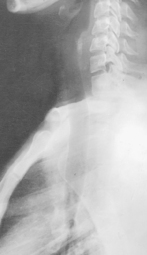

• Erect, seated or standing, center upper airway to CR

• Arms down, chin raised slightly

• To visualize neck region, include EAM at upper border of image.

• If distal larynx and trachea is of primary interest, center lower to include area from C3 to T5 (Fig. 1-18).